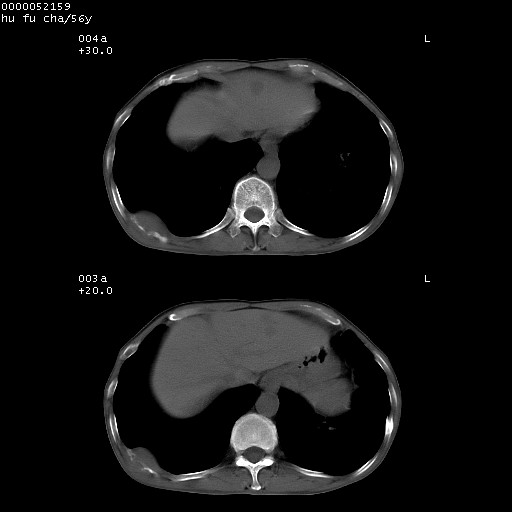

以下是引用zsl6918在2008-8-25 22:47:00的发言:[br]胸骨,胸椎及肋骨均可见多发转移表现,肝内低密度结节不除外转移。原发灶可能在右肺。双侧可见支扩表现。

以下是引用宇宙ct在2008-8-25 23:26:00的发言:[br][br] 胸骨,胸椎及肋骨均可见多发转移表现,肝内低密度结节不除外转移。原发灶可能在右肺。双侧可见支扩表现。 [br] [br]

以下是引用卜一在2008-8-26 8:02:00的发言:[br][br] 支持:肺癌并肺内,胸骨,胁骨,胸椎及肝内转移!另:左肺支气管扩张征伴感染! [br]

以下是引用zjzjr在2008-8-26 11:03:00的发言:[br]支持:肺癌并肺内,胸骨,胁骨,胸椎及肝内转移!另:左肺支气管扩张征伴感染!